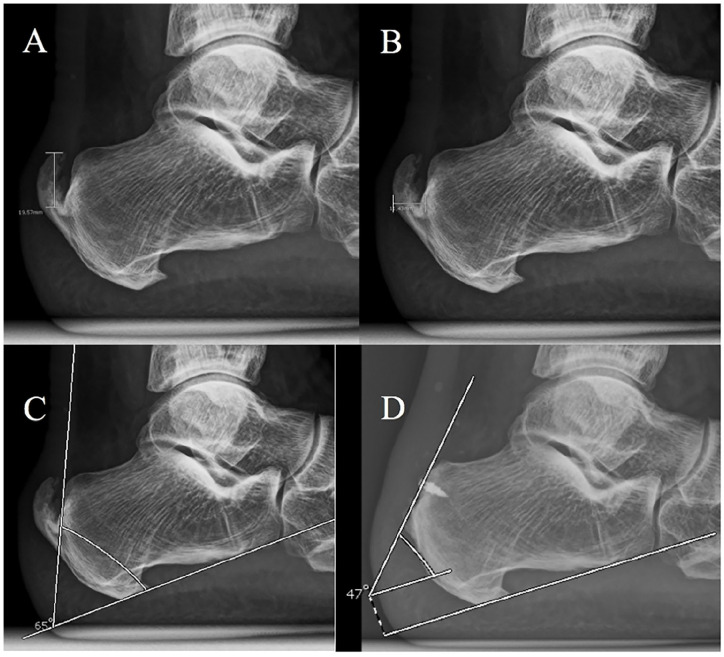

Methods: A retrospective cohort study was performed in order to determine clinical and radiographic outcomes of PMGR and ATDR for patients presenting with symptomatic calcified IAT, at a minimum follow-up of 30 months. Patient satisfaction was assessed at last available follow-up as very satisfied, satisfied, and unsatisfied. Clinical assessment was performed evaluating preoperative and last available follow-up visual analog scale for pain (VAS-P) and the Foot and Ankle Outcome Score (FAOS). Radiographic evaluation included Fowler-Phillip angle, calcification length, calcification width, and presence of Achilles IC, measured on standard weightbearing lateral calibrated radiograph of the foot preoperatively and last available follow-up evaluation for each patient.

Results: The mean follow-up was 46 (range, 30-72) months. We registered 45 "very satisfied" patients (84.91%), 6 "satisfied" patients (11.32%), and 2 "unsatisfied" patients (3.77%), as well as statistically significant improvement on both clinical scores tested. We found statistically significant differences between the initial evaluation and last available follow-up on all radiographic measurements. There was no significant radiographic recurrence of calcified IAT, whereas minor Achilles intratendinous calcifications were found in 10 patients (18.87%).